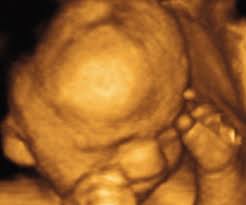

The exact time twins can be detected depends on the type of twins, for example, if they're identical (from one egg) or not. By eight weeks of your twin pregnancy, your babies will have buds for limbs that look like little paddles. Mehr als 200.000 maschinen sofort verfügbar. Most doctors will schedule an ultrasound somewhere between 6 and 10 weeks of pregnancy to confirm the pregnancy and check for multiples. Six full weeks is when you're 6+0 weeks pregnant. I should be 7 weeks, 4 days according to last period. (florida) i suspected i had twins because my beta numbers were high, i had two big follicles during my iui and i'm already big for less than 7 weeks! Seeing twins at 6 weeks is definitely possible. Besides ultrasound at 4 weeks, there are several changes during pregnancy for moms to expect. By four weeks, twins will start showing during ultrasound in form of 2 gestational sacs, but you cannot get clear indication of twins until 6 weeks. The first time i spotted but the other two were gushes. This was taken at 4 weeks 6 days. Some women would rather not know until both twins are relatively safe, while others want to know even if the chances of losing one twin are high.

Around six weeks, each baby's spinal cord and brain start to develop from their own neural tube. (florida) i suspected i had twins because my beta numbers were high, i had two big follicles during my iui and i'm already big for less than 7 weeks! This pole structure actually has some curve to it with the embryo's head at one end and what looks like a tail at the other end. What are the chances of having twins? You have approximately a 3.35 chance of having twins naturally , without the help of any fertility treatments. Besides ultrasound at 4 weeks, there are several changes during pregnancy for moms to expect. When you're 6 weeks pregnant with twins, you are between 5 weeks+0 days and 5 weeks+6 days pregnant. Taken at 4 weeks, the ultrasound image shows a gestational sac.

The fetal pole is the first visible sign of a developing embryo. Six full weeks is when you're 6+0 weeks pregnant. Get to know what you need to take care of when 4 weeks and 6 days pregnant pregnant. A full bladder provides an ultrasonic window to better see what's inside the uterus. Transvaginal ultrasound, by contrast, can detect pregnancies earlier, at approximately 4 ½ to 5 weeks gestation. Surprise twins at 20 weeks. This pole structure actually has some curve to it with the embryo's head at one end and what looks like a tail at the other end. I am going to have another one next week to confirm.

Between 5 ½ to 6 ½ weeks, a fetal pole or even a fetal heartbeat may be detected by vaginal ultrasound. In this 7th week of pregnancy, your baby's lungs are starting to develop. The ultrasound picture above is of identical twins who share a placenta at 6+2 weeks. Beauty points sammeln & mit der douglas beauty card von exklusiven vorteilen profitieren. This begins with a small lung bud branching out from the upper part of the tube (esophagus) between your baby's mouth. Get to know what you need to take care of when 4 weeks and 6 days pregnant pregnant. I've been posting in october 2012 since i found out i was pregnant in february. You have approximately a 3.35 chance of having twins naturally , without the help of any fertility treatments. They said the baby looked small and measured about 6 weeks. 4 weeks) between 5 ½ to 6 ½ weeks, a fetal pole or even a fetal heartbeat may be detected by vaginal ultrasound. Little arms and legs sprout. You don't hear heartbeats any earlier or later with twins, that i know of. Mehr als 200.000 maschinen sofort verfügbar.